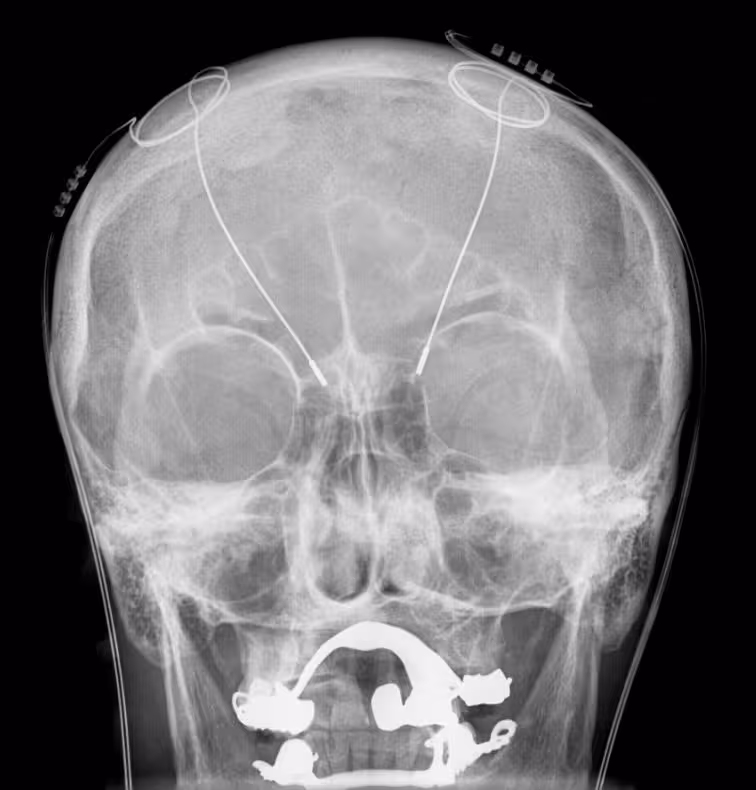

(science fiction) A person who has an electronic brain implant.

The wires of an implanted deep brain stimulation (DBS) device are visible as white lines in an X-ray of the skull. Large white areas around the maxilla and mandible are metal dentures and are unrelated to the DBS device.